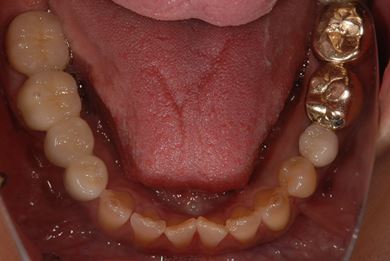

治療内容 メタルボンドセラミック(クラウン1本、ブリッジ3本、メタルボンドセラミック土台1本)+ハイブリッドセラミックインレー1本

治療部位

4

7 6 5 4

治療前

• 治療前